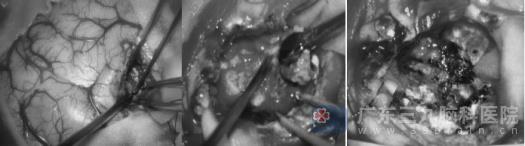

1月20日,卢阿姨在全身麻醉下接受左侧额岛叶高级别胶质瘤切除术,左侧额岛叶,是极其重要的神经功能区,主管运动性语言,还管左侧肢体的运动和感觉。神经外十科团队凭借精湛的显微技术精准操作,在高清显微镜下切除了肿瘤,保护了重要脑区和神经,手术过程十分顺利。术后,卢阿姨积极配合医护人员完成后续治疗与护理,恢复情况良好,于1月30日顺利出院居家休养。

术中照片